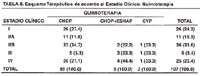

En la Tabla N° 8, cuando se analiza el esquema terapéutico de acuerdo al estadio clínico con relación a la quimioterapia, se puede apreciar con claridad que para la enfermedad localizada en el estadio clínico tipo I y IIA, el único esquema utilizado fue el de CHOP, sin embargo para el estadio IIB y con mayor frecuencia para los estadios III y IV, además del esquema de CHOP, se manejaron los pacientes con las combinaciones de CHOP + ESHAP, así como en algunos pacientes se utilizó el esquema CVP. Esto refleja la buena respuesta en este grupo de pacientes seleccionados de Linfoma Gástrico con estadios clínicos I y IIA, bajo el esquema de tratamiento quimioterápico con CHOP.

En la Tabla N° 9, cuando se analiza el manejo quirúrgico en los pacientes con Linfoma Gástrico de acuerdo a los estadios clínicos, se puede precisar que el manejo quirúrgico está reservado casi exclusivamente para los estadios clínicos I y II, siendo una excepción a la regla el manejo quirúrgico para los estadios clínicos III y IV con un paciente para cada estadio. En el caso del paciente con tratamiento quirúrgico de gastrectomía total para el estadio clínico IV, se trató de un paciente varón de 24 años con Linfoma Gástrico primario tipo T, con hemorragia digestiva recurrente que no respondió al tratamiento endoscópico repetido con argon plasma, inyección de adrenalina y solución salina y finalmente tampoco respondió a la inyección de alcohol absoluto. El otro caso, se trata de una paciente mujer de 60 años con estadio clínico III con Linfoma Gástrico primario a células B grande difuso, fue manejada con terapia combinada de gastrectomía total y CHOP, con buenos resultados, actualmente la paciente está viva y sin enfermedad.